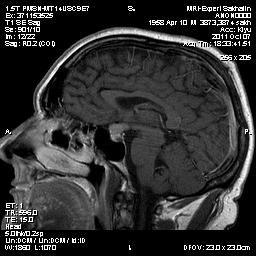

Аденома гипофиза

Вот такая аденома гипофиза сегодня.Мужчина с жалобами на снижение зрения.

Мне кажется что это все же не аденома, может глиома хиазмы ? (воронки гипофиза)? Или еще какое-нибудь объемное образование.... Что то меня смущает, еще не поняла что, но В любом случае наверное я бы однозначно не писала что это аденома, а выставила бы весь диф. ряд.

Танюша, обычно пишем "образование хиазмально-селлярной области"

Присоединяюсь к последнему коментарию, все таки откуда растет по моему мнению трудно однозначно сказать, лучше себя обезопасить написав "объемное образование хиазмально-селлярной области"